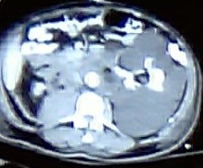

Multiple hepatic abscesses in other patients with cholecystocolic fistulas (Courtesy Dr. V. Penopoulos)